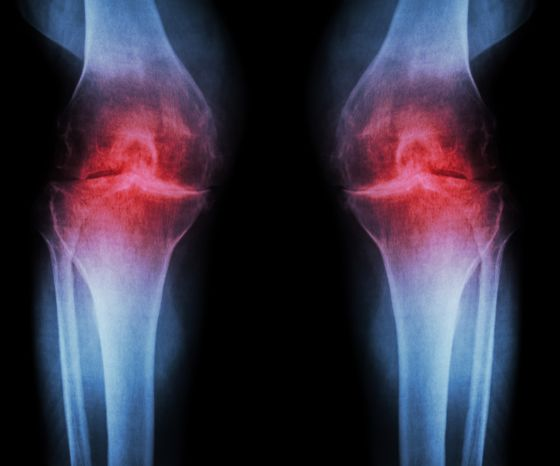

一、 X光:看的是“间隙”里的秘密

很多人误以为X光能直接看到软骨

其实,在X光的成像原理中,软骨是“透明”的

1. 为什么X光只看“间隙”?

X光的穿透力与物质密度有关

骨头密度大,吸收射线多,在底片上显现为白色;而软骨、韧带、积液这些含水量高的组织,密度低,射线几乎全穿过去了,在底片上就是一片漆黑

逻辑递进:

既然软骨看不见,医生怎么判断它磨损了呢? -> 看间隙

想象一下两块坚硬的砖头(骨头)之间垫了一层厚厚的透明橡胶垫(软骨)

X光下,你只能看到两块砖头,它们中间空出了一段距离

健康状态: 砖头之间的“黑缝”很宽,说明橡胶垫很厚

骨关节炎状态: “黑缝”变窄了,甚至两块砖头快撞在一起了,说明橡胶垫(软骨)已经磨损殆尽